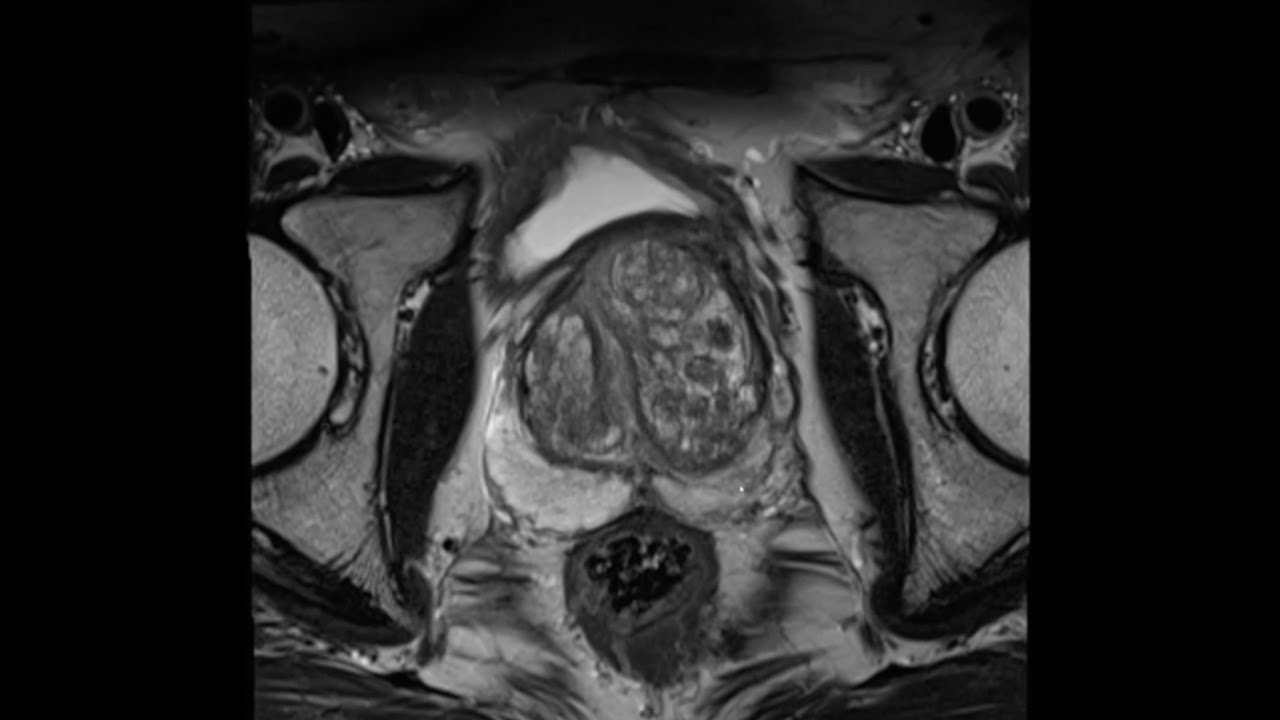

MRI Prostate Study Day

MRI Prostate Course to learn everything you need to know about image interpretation and reporting

✅Prostate anatomy

✅PIRADS v2.1 and Likert scoring

✅Over 30 interactive mpMRI prostate cases with feedback